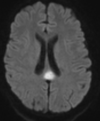

Qual a melhor sequência de RM para avaliar isquemia aguda?

A

DWI. Sensibilidade muito superior à TC (90 - 100%).